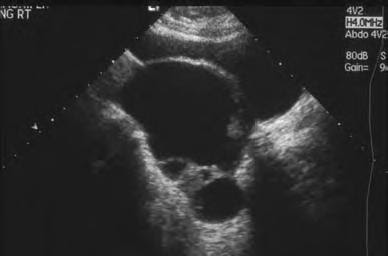

Endoscopia Ginecologica: Ecografía en cancer de ovario 😈